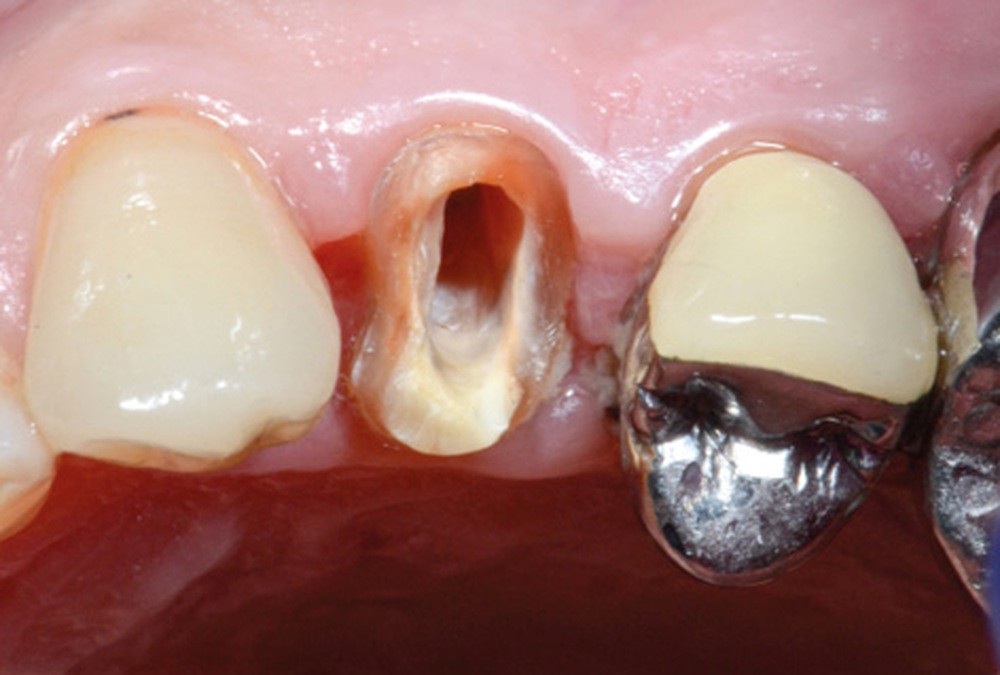

L’application stricte de ces règles élémentaires oriente donc préférentiellement, dans le cas de perte tissulaire modérée ou importante, vers la réalisation d’inlay-core (fig. 1a-b).